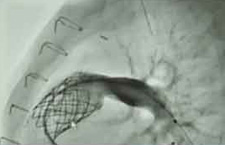

Kayla received one of the area’s first Medtronic Melody Heart Valves. The valve is inserted through a catheter in the groin to repair a damaged conduit. The conduit was surgically implanted when Kayla was a baby to correct blood flow from the heart. By successfully repairing the conduit with the new valve, inserted via transcatheter, Kayla was able to delay or avoid open heart surgery.